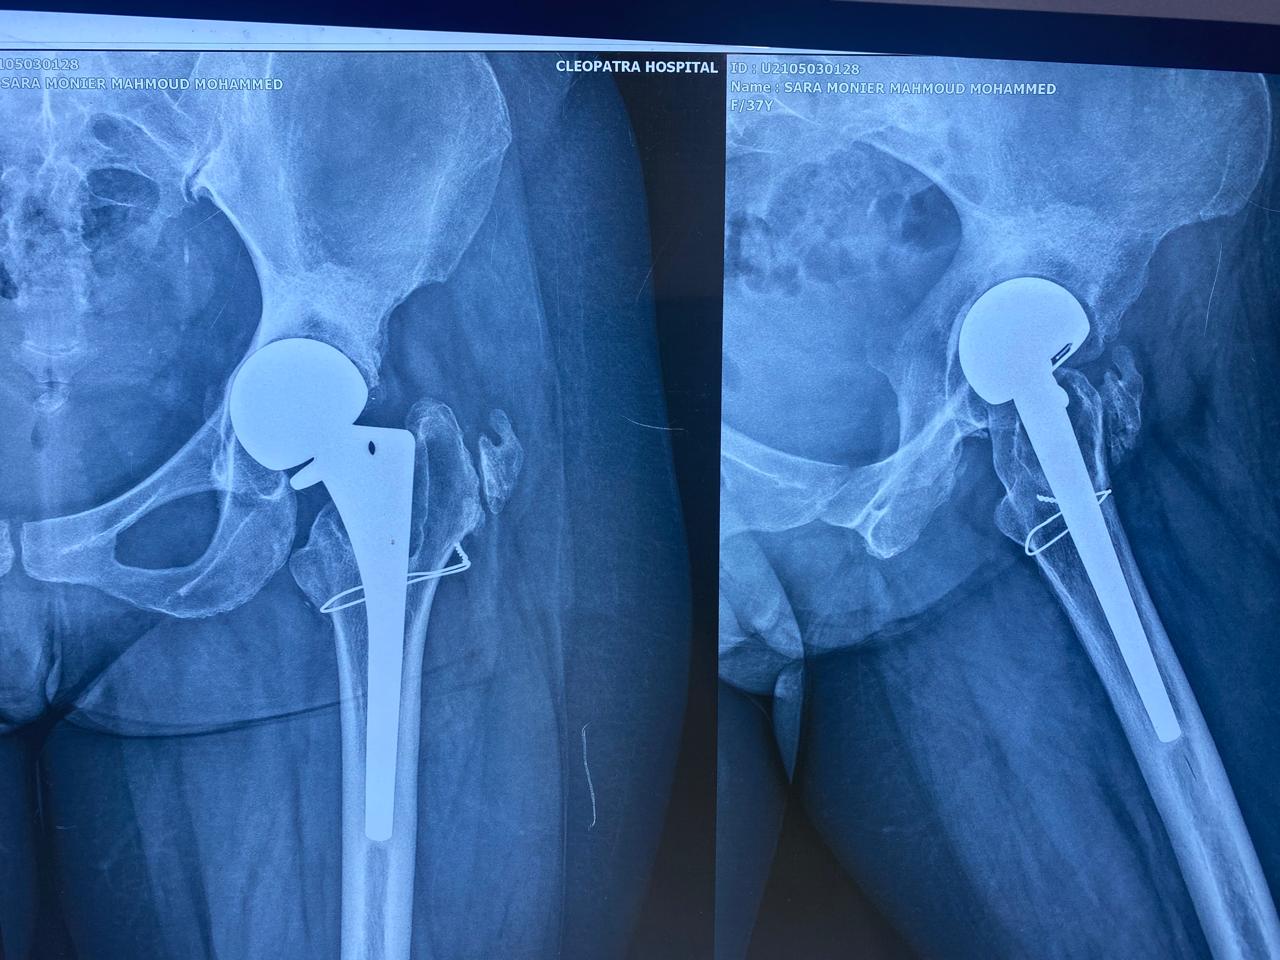

أجرت جراحة نصف مفصل بالحوض منذ ٢٠٠٦

تبين الأشعات وجود فجوات عظمية بالحق مع بروز داخلي لرأس المفصل مع وجود الام شديده.